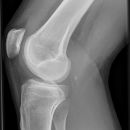

Kniegelenk